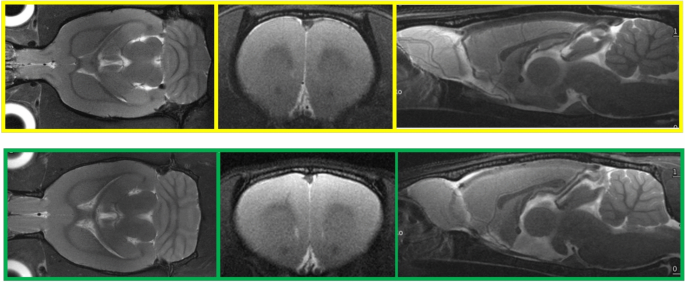

Anatomical images revealed a shorter, more ellipsoid-shaped brain in WKY/CMS rats compared to W/CTRL. This difference, particularly evident in the sagittal view (see Fig. 1), was consistently observed across all subjects (see Supplementary Fig. 1 for representative axial and sagittal images from each animal).

Comparison between W/CTRL (yellow, upper row) and WKY/CMS (green, lower row) rat brains by using T2W MRI (TR/TE = 2500/33 ms, one average, one repetition, matrix = 256 × 256, slice thickness = 1 mm, in coronal (15 slices, FOV = 30 × 25 mm2), axial (27 slices, FOV = 25 × 25 mm2) and sagittal (19 slices, FOV = 30 × 25 mm2) orientations).